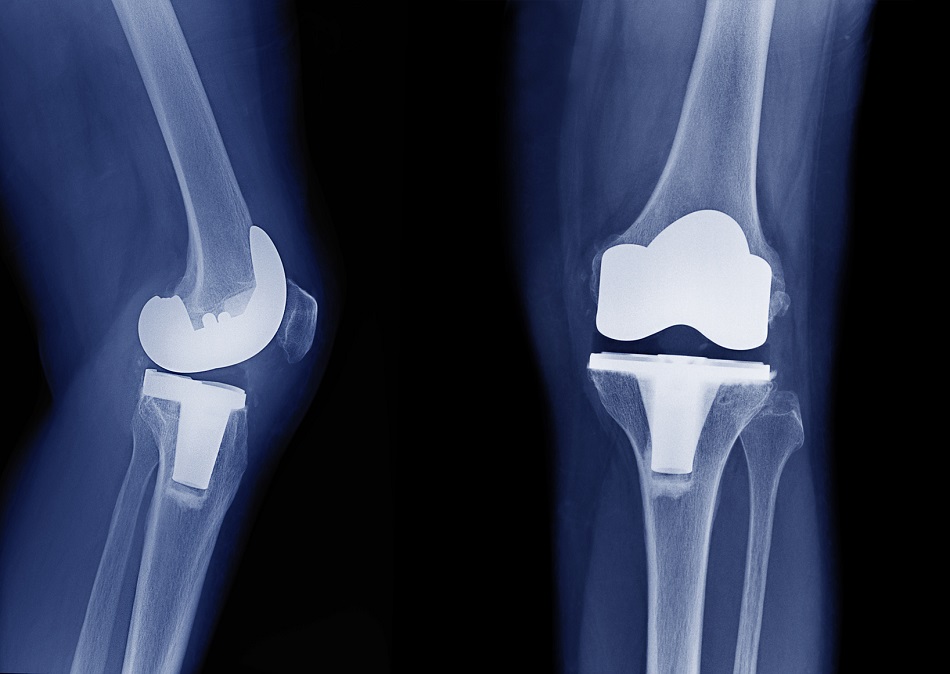

Consumo de opiáceos entre pacientes con artrosis grave de rodilla

En este  estudio de utilización de medicamentos se encontró que entre los pacientes daneses con artrosis de rodilla grave, la prevalencia y el uso total de opioides se duplicó durante los 5 años anteriores a al reemplazo de rodilla. Además, el 10% de la población de estudio fue responsable del 90% de los opioides utilizados. Eur J Clin Pharmacol, 13 de junio de 2022